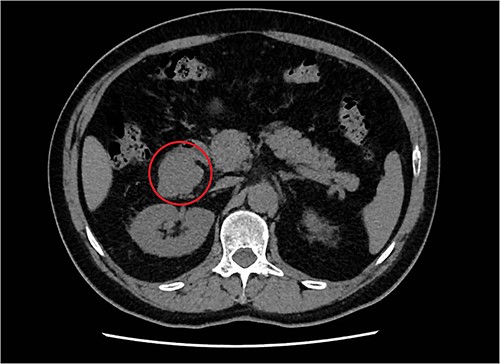

A 57-year-old male, with only a history of severe arterial hypertension, was admitted to our surgical department because of a retroperitoneal nodular mass measuring about 4 cm in maximum diameter, discovered on an abdominal echography. The ultrasonography was performed for the onset of a 1-year long vague abdominal pain at the right hypochondrium with posterior irradiation, without any other associated symptoms. Subsequently, he underwent total body enhanced CT scan, which confirmed the presence of a retroperitoneal polylobate neoformation developing in the right perirenal space, with maximum axial diameters of about 40 × 70 mm, which exerted a mass effect on the duodenum with which a thin adipose cleavage plane was present (Figs 1 and 2). The mass was rich of contrast impregnation in the early phase, which further increased in the portal phase. The presence of a vascular structure was highlighted posteriorly to the mass.

Transversal abdominal CT scan revealing a retroperitoneal polylobate neoformation in the right perirenal space.